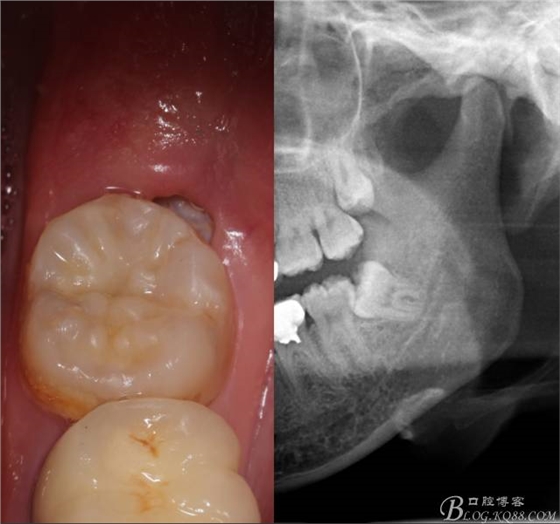

補完牙后,準備撥除阻生智齒了。

先分析智齒的情況,口內(nèi)直觀是半個牙尖都沒露出來,差一點就完全埋伏了。磨牙后墊的可操作面積中規(guī)中紀,X全景片示三類阻生,根冠比例是1:1,非融合根,近中根壓下頜管。